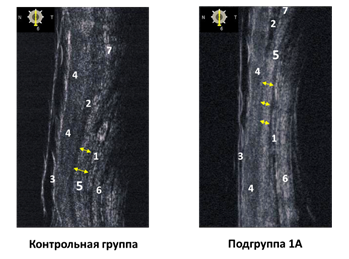

В результате ультразвукового исследования у 26 пациентов с апоневротическим птозом (1А) отметили истончение апоневроза леватора при сравнении с контрольной группой (рис. 4), а у двоих пациентов – отсутствие дистальной части апоневроза. Средняя толщина апоневроза леватора у этих пациентов составила 0,1 ± 0,067 мм при норме 0,21 ± 0,071 мм (p<0,05), а толщина мышцы Мюллера была незначительно меньше, чем в нормальном верхнем веке (0,19 ± 0,03 и 0,23 ± 0,027мм соответственно, p<0,05). Интраоперационно у этой группы пациентов визуализировали истончение апоневротических волокон, локальные дефекты и проводили фиксацию зоны сплетения апоневроза и тарзоорбитальной фасции к тарзальной пластинке. В случае недостаточного эффекта выполняли вскрытие тарзоорбитальной фасции и рефиксацию апоневроза.

Рис. 4. Обозначения: 1 – мышцы Мюллера; 2 – круговая мышца глаза; 3 – кожа; 4 – слой соединительной ткани; 5 – апоневроз леватора; 6 – склера; 7 – тарзоорбитальная фасция

Источник: составлено авторами по результатам данного исследования.